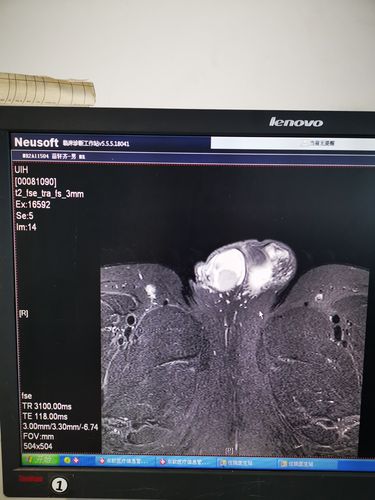

睾丸肿瘤切除术